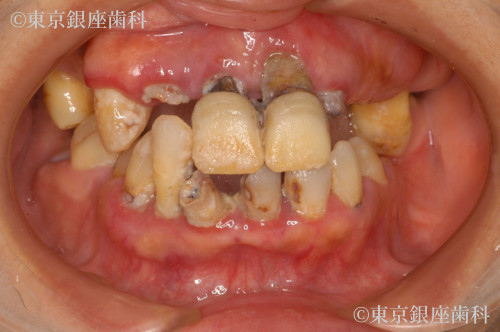

Before

疾患 歯牙部分欠損

幼少期からの歯科恐怖症で長期間治療を避けてきたが、家族の結婚式のため治療を決断。丁寧な説明で不安を軽減し、ワンデイインプラントで当日に仮歯を装着したことで自然な見た目で式に参加できた。

ワンデイインプラント(上下)